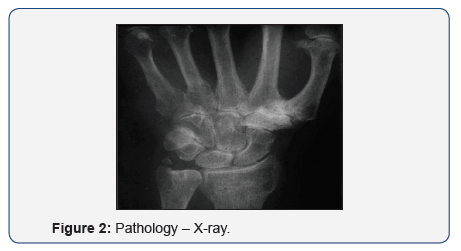

Pathology

Stage I:

- Pain

- Synovitis

- Local Swelling

- Effusion into the joint (Figure 2)